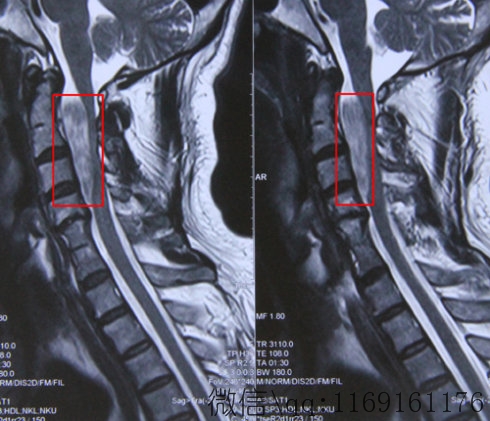

颈椎病的X线片检查通常作为确诊的常规检查,对鉴别诊断、选择治疗措施、观察疗效和判定预后有一定的帮助。作为一般规律,临床表现和X线片上的变化常常是相互对应的。但是在临床实际工作中,有时也会出现X线片变化与临床表现不相符合的现象,例如:某些患者具合明显的行走不稳,而X线片上却未显示相应的椎体后缘骨质增生;上肢有疼痛、麻木的感觉,而X线片上椎间孔并无狭窄;头晕症状明显,而X线片上钩椎关节骨质增生不明显等。这种X线片上的变化与临床表现相矛盾的现象是什么原因造成的呢?

首先,由于X线本身特点,它对骨组织等高密度组织分辨较为清晰,而对某些组织,如韧带等软组织显影就相对不明显。例如:刺激或压迫脊髓、脊神经根并可产生明显临床症状的髓核突出或脱出,黄韧带和后纵韧带纤维化、肥厚、硬化等,在X线片上则有可能表现不明显。此外,由于水肿、肿胀、渗出、粘连等反应性炎症刺激和压迫脊神经根产生上肢疼痛等症状,在X线片上也不一定能表现。本身有动脉血管硬化症基础,或是因自主神经系统原因,也可对椎动脉型颈椎病“雪上加霜”,而使症状较严重,但X线片上钩椎关节骨质增生不明显。相反,单纯的骨质增生若未累及脊髓、神经、血管,也可无症状,而造成临床表现与X线片上的变化相矛盾。

当然,对于这种矛盾现象并不是难以解决的。除了X线片,通过系统病史的询问、全面的物理检查及借助于较先进的医疗仪器,如CT、磁共振成像等加以综合分析,对颈椎病的诊断及分型并不是很困难的事。